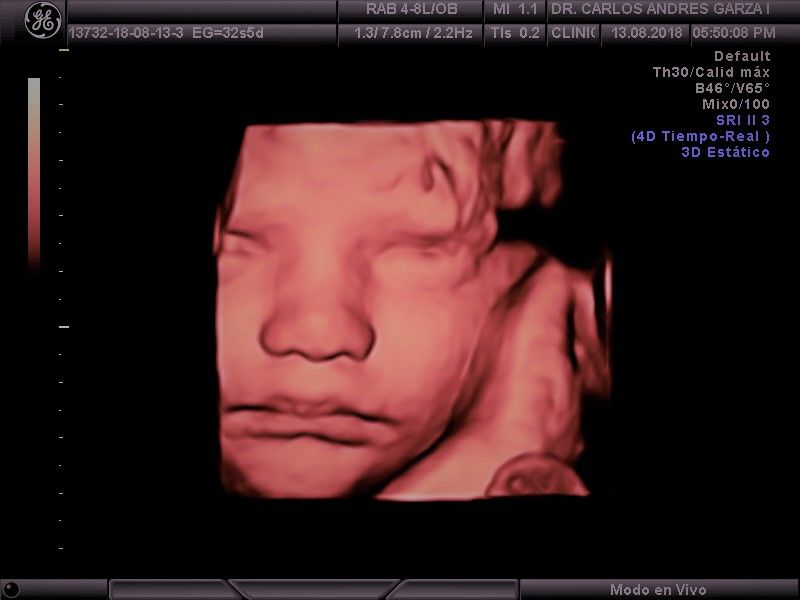

Ultrasonido 4D

!Conoce a tu bebé hoy¡ Se trata de la última tecnología en ecografía o ultrasonido a nivel mundial, que consiste en un procesamiento de reconstrucción digital de imágenes para formar una sola imagen en 4 dimensiones, permitiendo así poder visualizar cualquier estructura tal cual la estuviésemos viendo directamente el rostro de tu bebé, antes de nacer. Con esta nueva generación de tecnología del ultrasonido puedes observar datos mas detallados de su bebé, sus movimientos, gestos, risas, bostezo, etc... tal como si lo tuviera en sus brazos. En el pasado los papas no conocían la cara de su bebe hasta que naciera.

Asistencia y control al parto

Llevamos el control de tu embarazo hasta el término del mismo, con la mejor tecnología en cuanto se refiere al ultrasonido 4D, que nos permite revisar de una mejor manera a tu bebé, atendiendo parto o cesárea en los hospitales de la región.